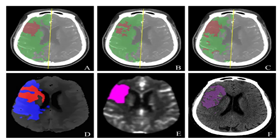

AI人工智能 & 算法服务

团队绝大多数都是数学专业毕业的,拥有20余年的原创性算法设计和开发经验,所有算法都已应用于大中型企业,一些算法填补了业界空白。在算法方面为软件企业和需求方提供基于具体场景的算法设计和开发服务,包括但不限于视觉识别方面的人工智能算法。